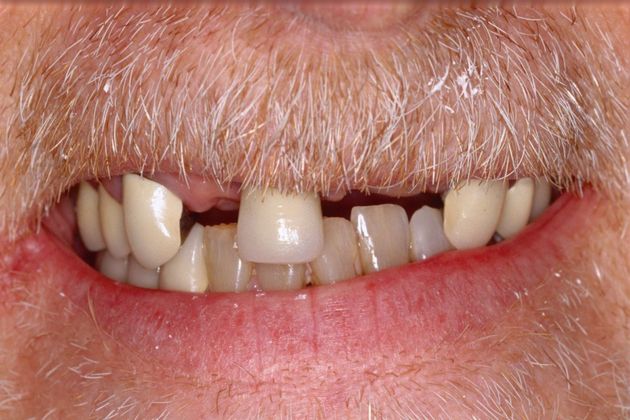

Procedures; Bite correction, gum recontouring, implants, whitening and crowns.

This healthcare professional had been wearing a removable appliance for years. He had a deep overbite and the anchor teeth for his appliance were breaking down. His main concern was to restore the functionality of his teeth with a fixed, long term solution.